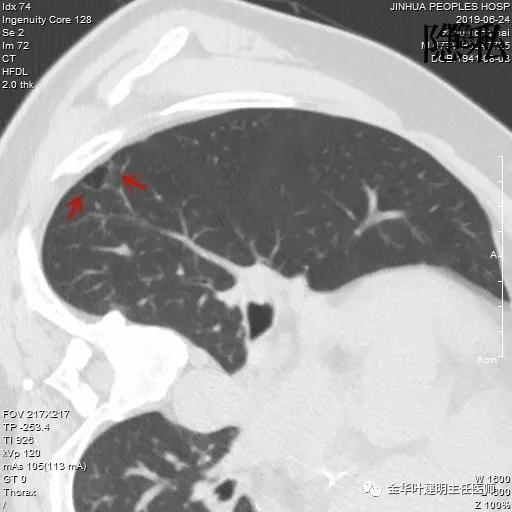

以上是2018年5月的片子,此处也呈空腔性病灶,但也点像是个肺大泡,因为绿色箭头所指处也有肺大泡。